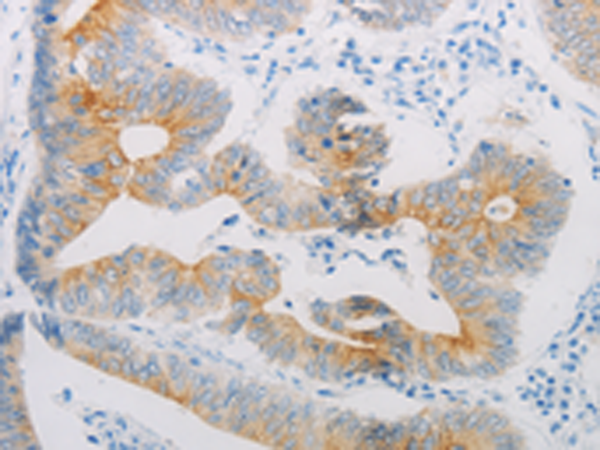

分类: 科研抗体货号: P10648别名: BAR, B2AR, ADRBR, ADRB2R, BETA2AR应用: WB,IHC反应种属: Human, Mouse